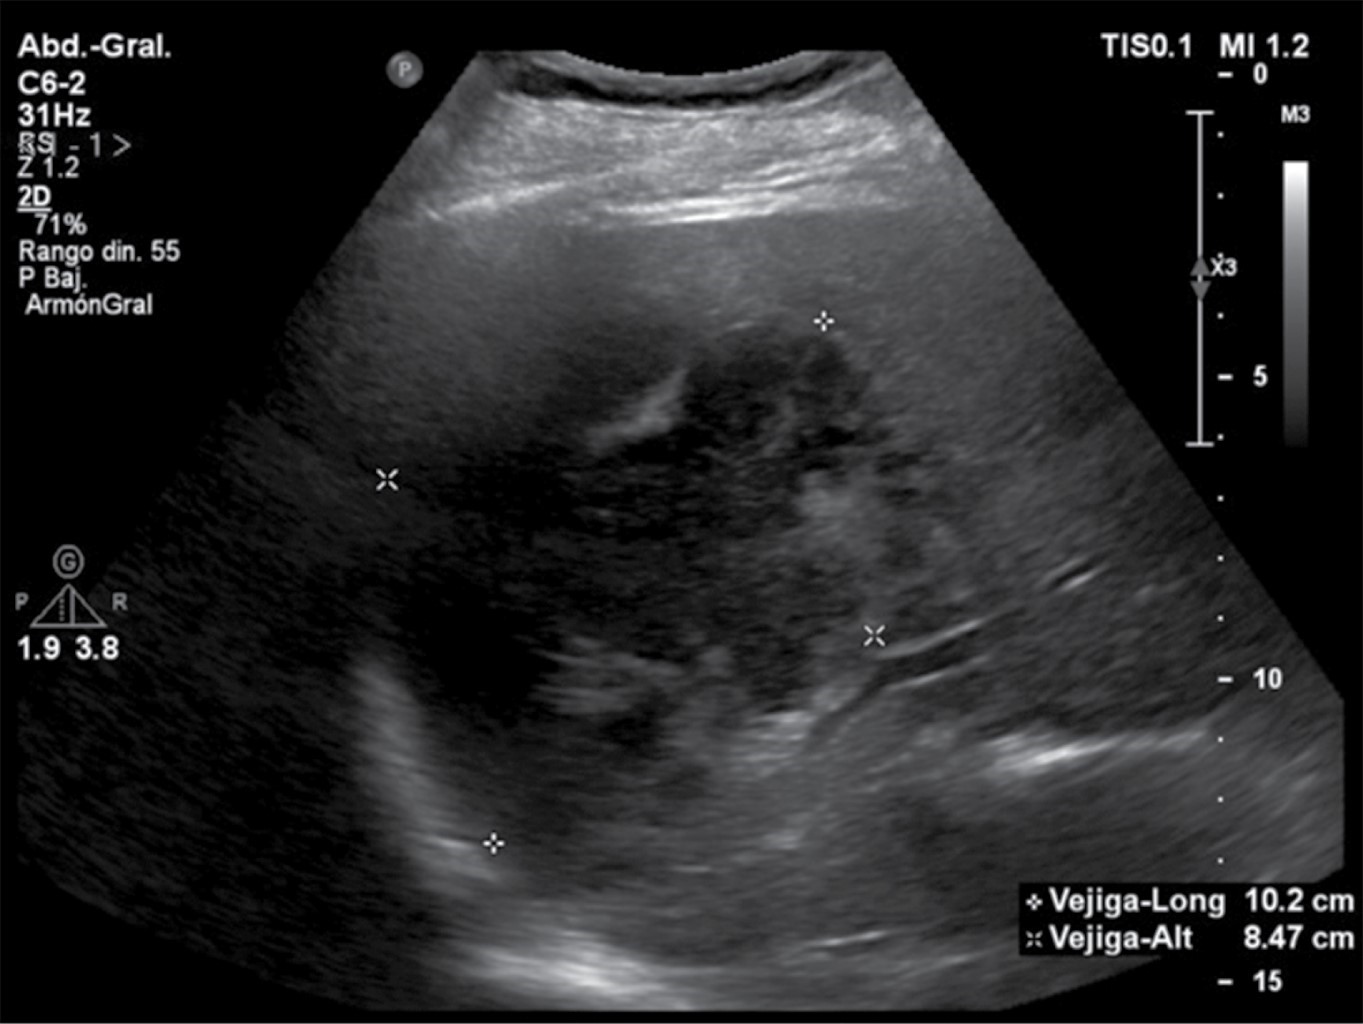

Debido a los hallazgos laboratoriales encontrados, se solicitó estudio de ultrasonido en búsqueda de foco infeccioso donde se identificó, en lóbulo hepático derecho, colección heterogénea ovoidea de bordes lobulados de predominio anecoico con imágenes ecogénicas lineales en su interior con dimensiones aproximadas de 10.2 × 8.4 × 7.5 cm, volumen de 341 cm3 a considerar en relación con absceso (Figura 1).

Figura 1